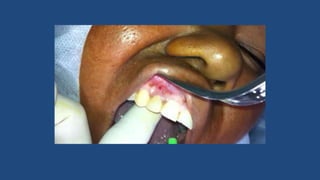

Drenagem de Abscessos – Técnica

Cirúrgica

• Escolher o ponto de flutuação

• Mais inferior possível

• Ser o mais estética possível

• Deve ser ampla o suficiente para propiciar a

drenagem de todas as lojas do abscesso

• Deve abranger todos os espaços fasciais

envolvidos, se necessário fazer múltiplas incisões

• Anestesia por bloqueio quando possível

Drenagem Cirúrgica

Drenagem de Abscessos– Técnica Cirúrgica • Escolher o ponto de flutuação • Mais inferior possível • Ser o mais estética possível • Deve ser ampla o suficiente para propiciar a drenagem de todas as lojas do abscesso • Deve abranger todos os espaços fasciais envolvidos, se necessário fazer múltiplas incisões • Anestesia por bloqueio quando possível